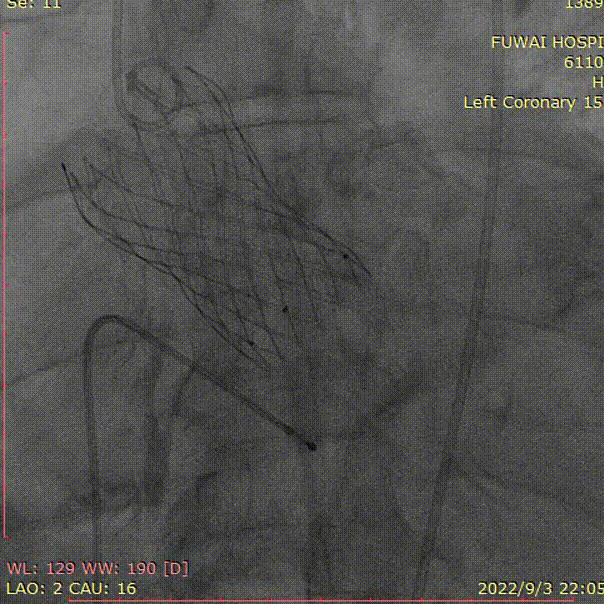

左冠造影